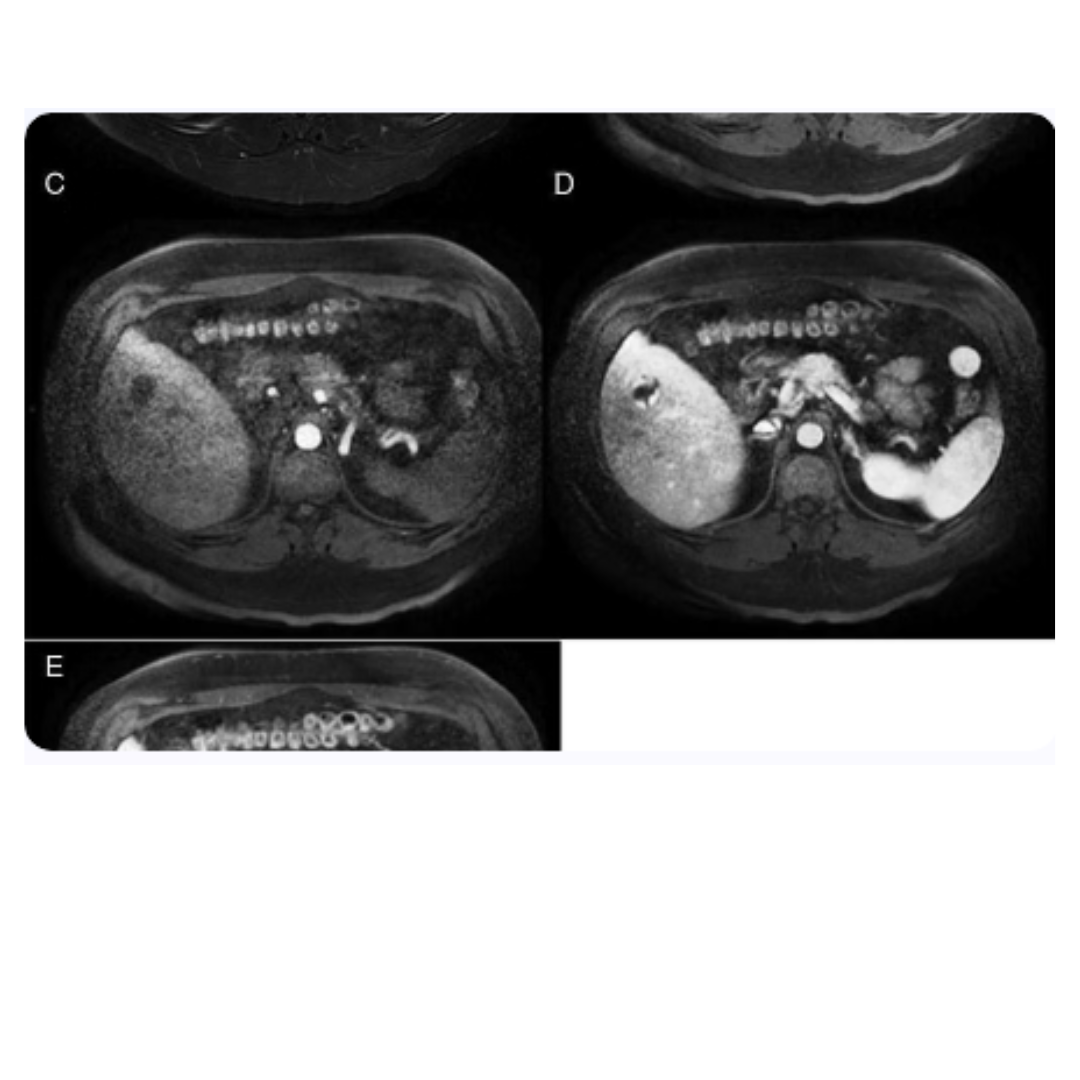

Resonancia magnética cerebral

La resonancia magnética (RM) cerebral es una herramienta avanzada en la detección de alteraciones intracraneales asociadas a la leucemia linfocítica aguda (LLA). La capacidad de la RM para brindar imágenes detalladas de estructuras blandas resulta esencial para identificar la posible infiltración leucémica en el sistema nervioso central (SNC), un paso crítico para planificar un abordaje terapéutico adecuado para estos pacientes.